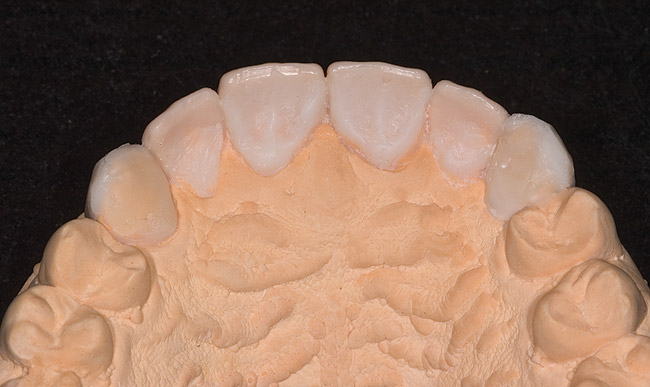

Figure 8  Palatal anatomy restored with wax on stone model.

Figure 8